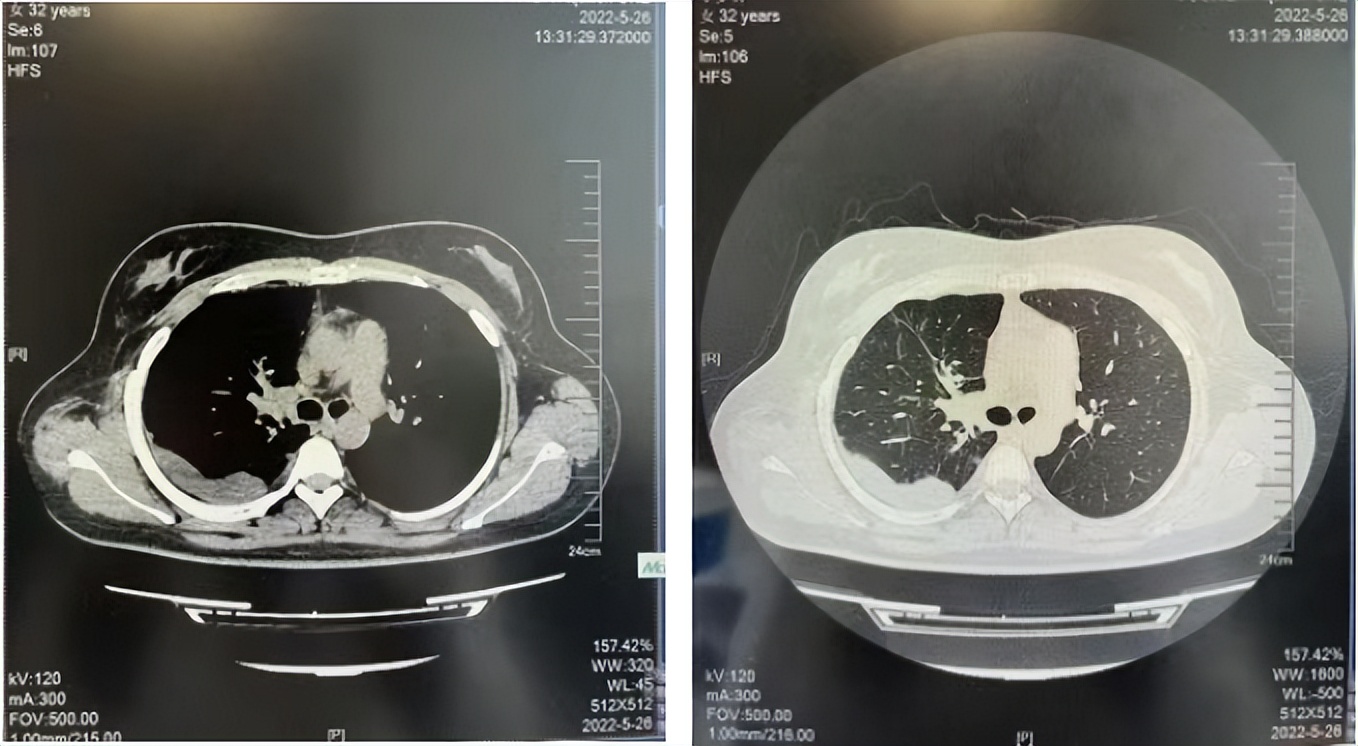

2016年1月复查CT提示支气管截断可见新发小结节,一线治疗采用培美曲塞+DDP方案化疗4周期(培美曲塞3.36,DDP 480mg)。化疗后复查胸部CT:右肺见不规则结节样影,最大层面大小约19mm*8mm,较前比较明显增大,疗效评估PD。2017.3-2017.4予单药多西他赛化疗3周期,疗效评估SD。2018年5月末复查CT提示结节较前增大,评效为PD,2018年6-10月予多西他赛+CBP化疗4周期,疗效评估SD。2022年5月患者出现活动后气短,复查胸部CT示右肺膨胀不良;右侧胸腔积液增多。胸腔积液包埋病理示符合肺腺癌细胞。行NGS基因检测:EML4:exon13-ALK:exon20融合。PD-L1(克隆号22C3)TPS<1%。

2018.07

2022.05

2022.08

2023.05

2024.12